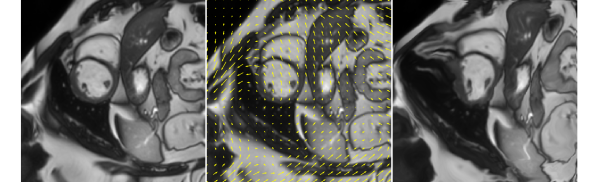

(a) image ()

(b) additive intensity

(c) transformed

field ()

image ()

(i) Transformed images are obtained by applying additive intensity fields produced by Generator .

(ii) Transformed images are obtained by applying random contrast and brightness values.